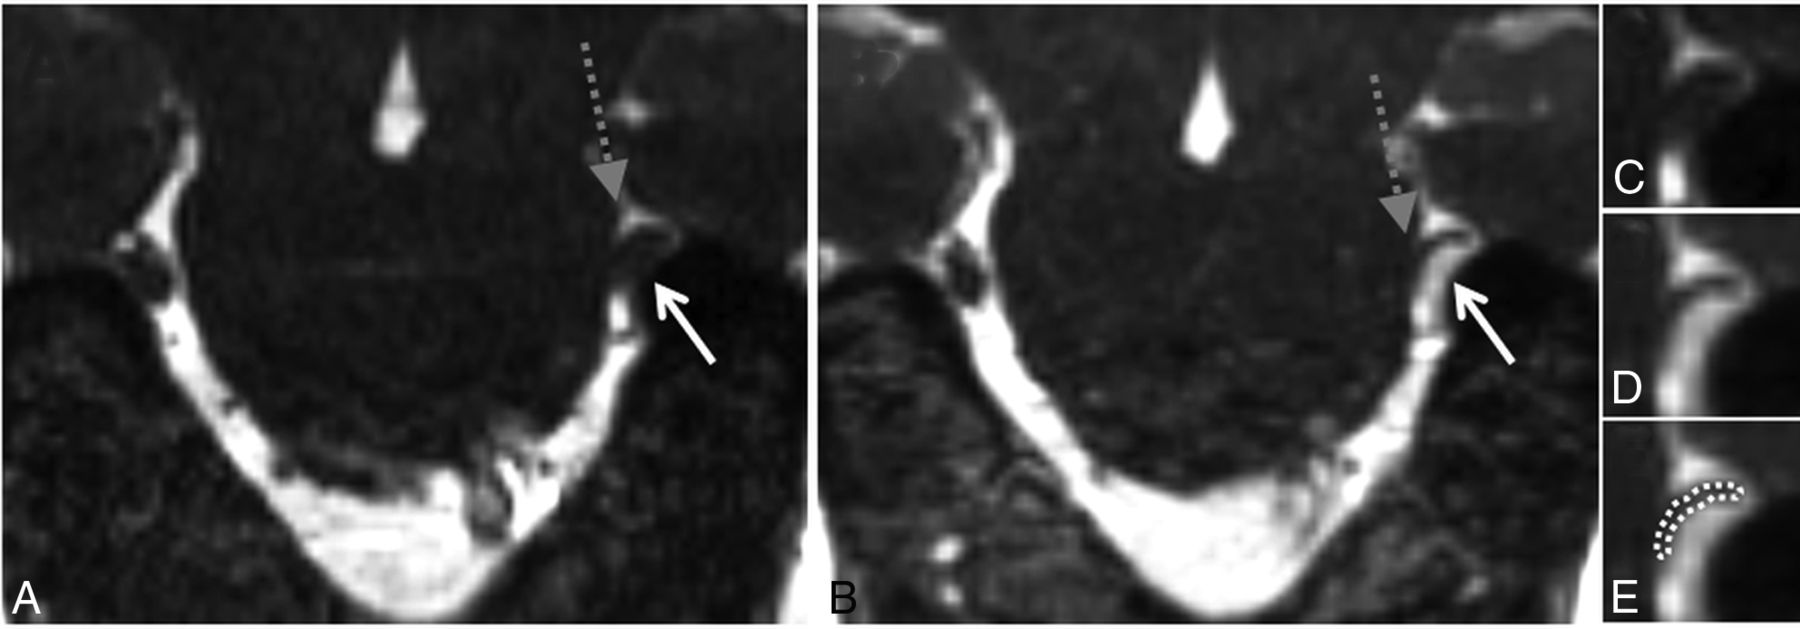

High-grade neurovascular conflict. Coronal NE-CISS (A) and CE-CISS (B) images show compression of the distal cisternal segment of the patient's left trigeminal nerve (gray dashed arrow) by a branch of the superior petrosal venous complex from below (solid white arrow). On the unenhanced image (A), the nerve root is not well-distinguished from the compressing venous branch. After contrast administration (B), the venous branch fills with contrast, showing a severely compressed unenhanced adjacent trigeminal nerve root at the level of the porus trigeminus. Zoomed-in images of the site of neurovascular conflict in the coronal plane (C–E) illustrate the poor contrast between vessels and nerve on the NE-CISS image (C) and the improved contrast after administration of gadolinium contrast material (D), allowing more confident delineation of the compressed nerve from the adjacent vessel (E). In this patient, grade 2 was given on the NE-CISS and grade 3 was given on CE-CISS images. On the patient's right, grade 1 was given on both the NE-CISS and CE-CISS images.